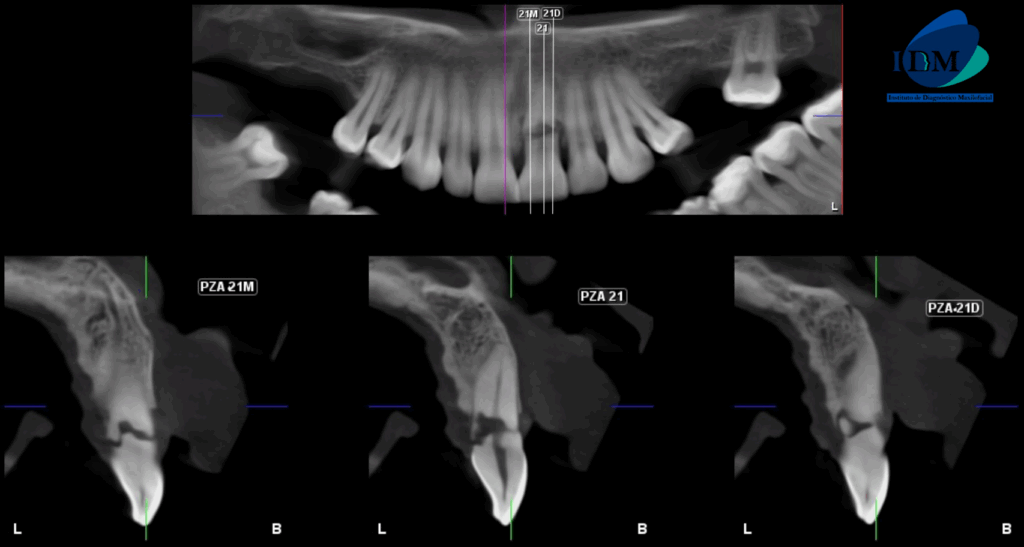

A la evaluación de la tomografía volumétrica (CBCT) en los cortes axiales (Figura 2) y transaxiales (Figura 3), se aprecia trazo hipodenso horizontal a nivel del tercio cervical radicular ocasionando separación de dos fragmentos

CORTES TRANSAXIALES

CASO 315 IDM cortes transaxiales